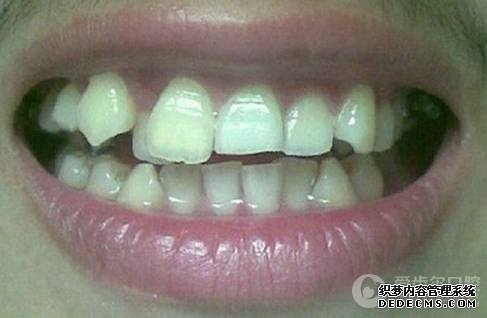

患者自述:眼看快到而立之年,身边好友都已成家立业,可我依然孤身一人,难免有些落寞。可是因为牙齿不齐,让我总是缺乏自信,性格也变得内向腼腆,几次相亲都被心仪的女孩拒绝。为了不被自卑心吞噬,我决定通过牙齿正畸改变自己,给自己一次幸福的机会。

矫正前旧照

矫正前照片